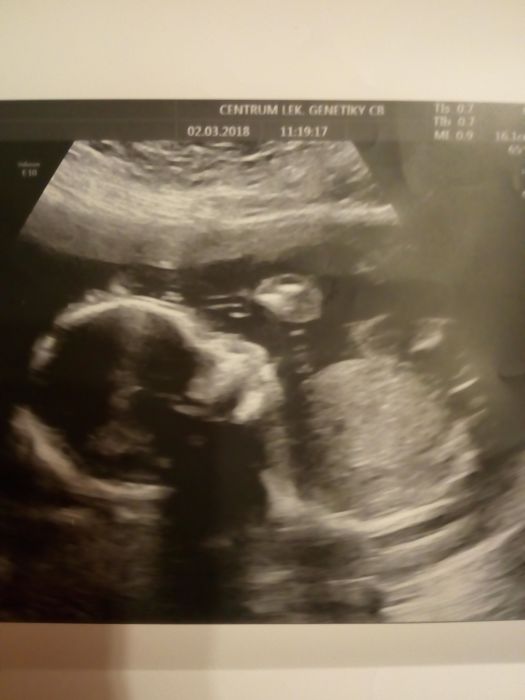

Ahojki, tak jsem byla dneska na velkem UTZ. Miminko je v poradku, nic mu nechybi

a je to holcicka. Dalsi. Kluk (17let) je trochu zklamanej, ale uz rezignoval. Po dvou sestrach a osmi sestrenicich (zadny bratranec) ....